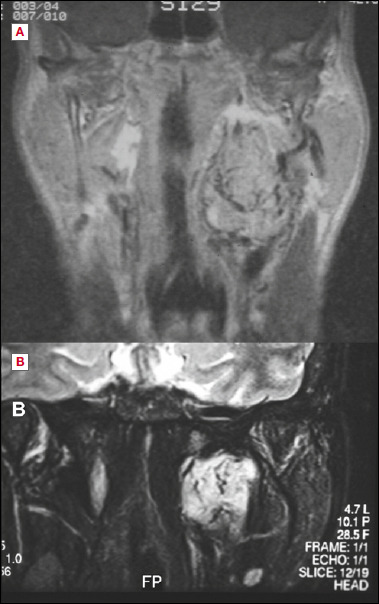

目的:探讨显微外科入路治疗咽旁间隙(PPS)肿瘤的安全性和有效性。第二个目的是评估术前和术后最终组织病理学诊断之间的对应关系。方法:对1985年至2022年间在2个三级转诊中心采用显微外科颈腮腺入路治疗的连续系列原发性PPS肿瘤进行分析。样本包括94例患者的97个肿瘤(88个良性和9个恶性),其中11例在我们中心首次诊断时患有复发性肿瘤。手术入路,根据假定的术前诊断,是包膜和整体切除(包括保守或根治性切除PPS)。结果:在97个肿瘤中,有88个肿瘤被完全切除。PPS显微手术后复发8例(多形性腺瘤4例,恶性神经鞘瘤2例,黑色素瘤1例,血管外皮细胞瘤1例)。8例复发病例中有4例在我们中心首次发现时是复发病例。术前诊断与最终组织学完全一致只发生在良性病变组,如副神经节瘤、神经鞘瘤或脂肪瘤,并行包膜切除。结论:显微外科手术可以通过狭窄的手术通道增加手术空间,改善对关键切割面、血管和神经的剥离,并允许显露病变的尾侧和颅侧范围,从而支持经颈腮腺入路。在我们的研究中,包膜和整体切除PPS对大多数患者都是有效的。在高级别恶性肿瘤中,除PPS壁外更广泛切除的病变可能包括血管和神经,应准确平衡适应证。

Objective: To investigate safety and efficacy of the microsurgical approach to parapharyngeal space (PPS) tumour. A secondary goal was to evaluate the correspondence between preoperative and final histopathologic diagnosis after surgery.

Methods: A consecutive series of primary PPS tumours treated between 1985 and 2022 in 2 tertiary referral centres with a microsurgical cervico-parotid approach was considered. The sample included 97 tumours (88 benign and 9 malignant) in 94 patients, of which 11 affected by recurrent tumours when first diagnosed at our centres. The surgical approaches, planned on the presumptive preoperative diagnosis, were pericapsular and en bloc resections (including either conservative or radical resections of the PPS).

Results: Pericapsular and en bloc resections of the PPS achieved complete removal in 88 out of 97 tumours. Relapses after PPS microsurgery occurred only in 8 cases (4 pleomorphic adenomas, 2 malignant schwannomas, one melanoma, and one haemangiopericytoma). Four of the 8 relapsed cases were recurrent cases when first seen at our centres. A complete correspondence between preoperative diagnosis and final histology occurred only in the group of benign lesions classified as paraganglioma, schwannoma, or lipoma, submitted to pericapsular resection.

Conclusions: Microsurgery may support the transcervical-parotid approach, by enhancing the operative space through narrow surgical corridors, improving dissection on critical cleavage planes, vessels and nerves, and allowing the exposure of both caudal and cranial extent of the lesions. In our series, pericapsular and en bloc resections of the PPS were effective in most of the included patients. In high-grade malignancies, where the morbidity of a wider resection beyond the PPS walls may include vessels and nerves, the indication should be accurately balanced.